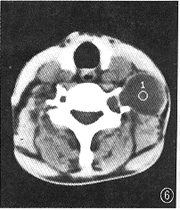

1.肿瘤CT增强影像表现特殊,可分为以下几类:(1)低密度区中伴团状高密度改变24个(图1),病理改变为在比较广泛分布的疏细胞区(Antoni B区)组织中,有相对集中分布的富细胞区(Antoni A区)(图2)。(2)弥漫点状改变20个,点状大小从1~4 mm不等,其密度不等。高密度CT值为60~80 HU,低密度为40~45 HU,两者CT值相差约20 HU。其中呈低密度点状4个;高密度点状4个;高、低密度混杂点状12个(图3)。此20个肿瘤中8个伴有1~2个形态不规则的低密度裂隙样变。高低密度混杂点状分布的病理改变为的Antoni A区、Antoni B区相互交错,分布均匀(图4)。低密度点状改变为比较广泛分布的Antoni A区或胶原基础上出现的零星分布的Antoni B区或微囊集中处,Antomi B区或微囊分布较集中时,即表现为低密度裂隙样改变。较广泛分布的Antoni B区伴少量Antoni A区或胶原则呈高密度点状改变。(3)低密度环伴中央弥漫不同密度点状改变5个,其中单纯为低密度点状或单纯为高密度点状各1个。此低密度环在病理上由Antoni B区组成。(4)中央低密度伴有环形改变8个(图5),环壁厚,环表现各异,其中表现为高、低密度混杂点状分布的3个,单纯低密度点状或高密度点状各2个,环与肌肉呈等密度1个。肿瘤中央的低密度区病理上由Antoni B集中区和(或)陈旧性出血区组成。(5)密度均匀的12个肿瘤中,等密度与低密度各5个,囊性变2个。在病理上等密度多由Antoni A区及胶原组成,Antoni B区较少,分散在Antoni A区及胶原间;而低密度肿瘤(图6)为均匀一致的Antoni B区及部分陈旧性出血组成,几乎无Antoni A区细胞(图7)。囊性肿瘤巨检时见黄色液体流出,囊壁上仍见典型Antoni A、Antoni B区改变。(6)增强特别明显的肿瘤3个,其中2个为弥漫点状改变(图8),1个为厚环。病理显示此3个肿瘤由丰富的Antoni A区组成,夹杂有微囊,而Antoni B区少见(图9),其中仅2个血供比较丰富。

图6 左颈神经鞘瘤增强扫描,肿瘤呈均匀低密度改变,CT值39 HU

图7 肿瘤病理学(HE ×40)表现。肿瘤为均匀一致的Antoni B区(淡色区)及少量陈旧性出血(深色区),基本上无Antoni A区